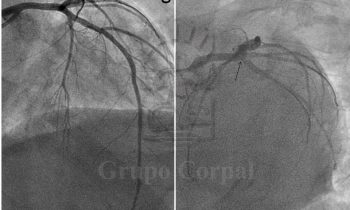

Insuficiencia cardíaca congestiva

Blog Cardiológico

por Grupo Corpal | 2 Dic, 2021 | Blog Cardiológico, Imagen del mes

Insuficiencia cardíaca congestiva Insuficiencia cardíaca congestiva como equivalente anginoso en la enfermedad severa del tronco coronario izquierdo. Se presenta el caso de un varón de 65 años de edad, hipertenso,...

by Grupo Corpal 2 Dic, 2021